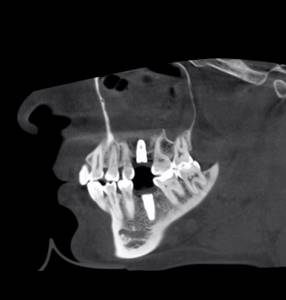

Как на фотографии выше – из-за целого ряда вмешательств и существовавшего ранее ороантрального соустья можно сказать, что от слизистой оболочки верхнечелюстной пазухи почти ничего не осталось. Можем ли мы как-то закончить эту работу? Легко:

Вкратце, причина в том, что при “крестальном” синуслифтинге у нас отсутствует какой-либо вменяемый контроль за состоянием слизистой оболочки гайморовой пазухи и, в случае возникновения перфорации, мы не сможем её увидеть и, соответственно, устранить без специальной эндоскопической техники, которая, как вы понимаете, у стоматологов обычно не водится. А, я напомню, что именно повреждение шнайдеровой мембраны, замеченное или незамеченное, является основной причиной послеоперационных осложнений при синуслифтинге. Визуальный контроль за состоянием этой самой мембраны – это и есть профилактика осложнений при синуслифтинге. А он возможен только в случае правильно спланированного доступа и при хорошем обзоре. То есть, при правильно проведенном “открытом” синуслифтинге.

Первая операция – мы не можем сразу поставить имплантат из-за почти полного отсутствия кости между полостью рта и дном верхнечелюстной пазухи:

Через 3 месяца – вторая операция – установка имплантата в сформированный объем костной ткани:

Как видите. восстанавливается всё очень легко, никаких дефектов не остаётся, но при этом мы получаем важное преимущество: достаточную свободу движений при формировании субантральной полости и хороший визуальный контроль за состоянием слизистой оболочки. Никакая нажопная оптика или суперпупермикроскоп, к сожалению, не обеспечат подобный контроль при закрытом синуслифтинге. Да, операция получается травматичнее и масштабнее, чем “закрытый” синуслифтинг, но несёт в себе гораздо меньше рисков.

Если сделать КЛКТ на этом этапе (через 2-3 недели после операции), то иногда мы можем увидеть утолщение слизистой оболочки в области дна альвеолярной бухты, вплоть до рентгенологической картины гайморита:

однако, в течение последующего месяца (при соответствующей терапии) рентгенологическая картина возвращается к нормальной:

Еще раз подчеркну, что причиной всего этого чаще всего является именно перфорация шнайдеровой мембраны. Если вы её не заметили во время операции – это не значит, что её нет.